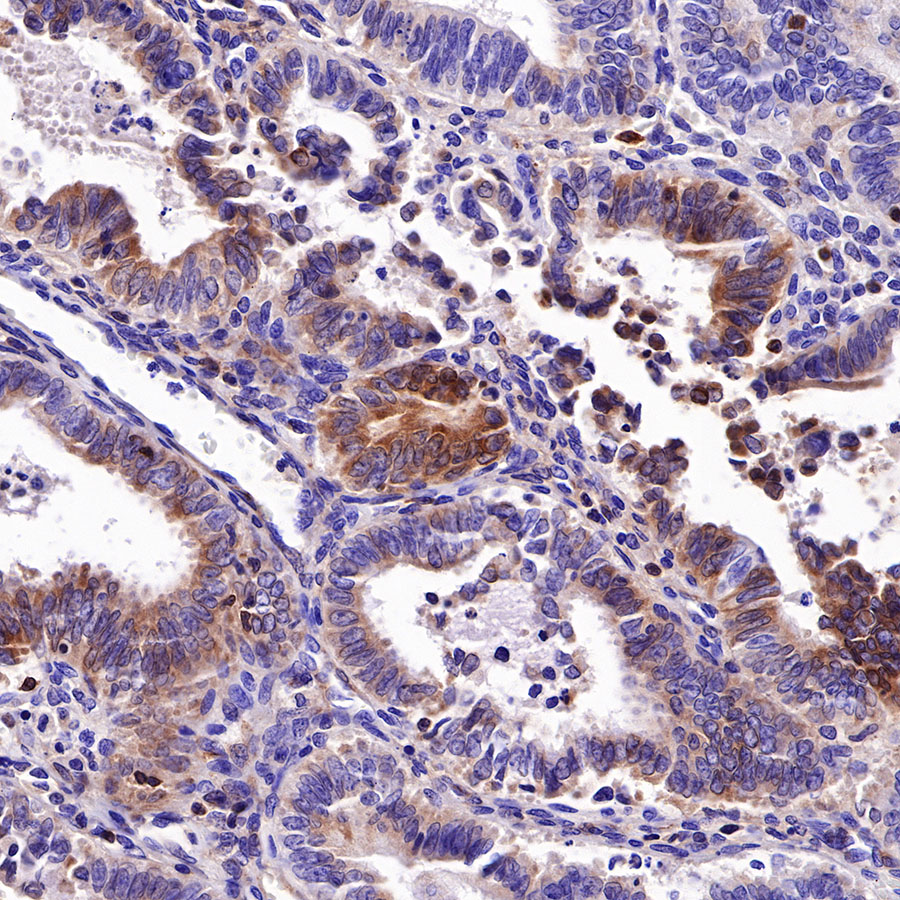

Picture

Picture

Immunohistochemistry